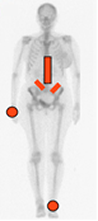

Fig 53. Distribución de la artropatía por psoriasis.

Compromiso dorsolumbar, simétrico de las sacroiliacas y de las falanges distales de las manos y los pies.